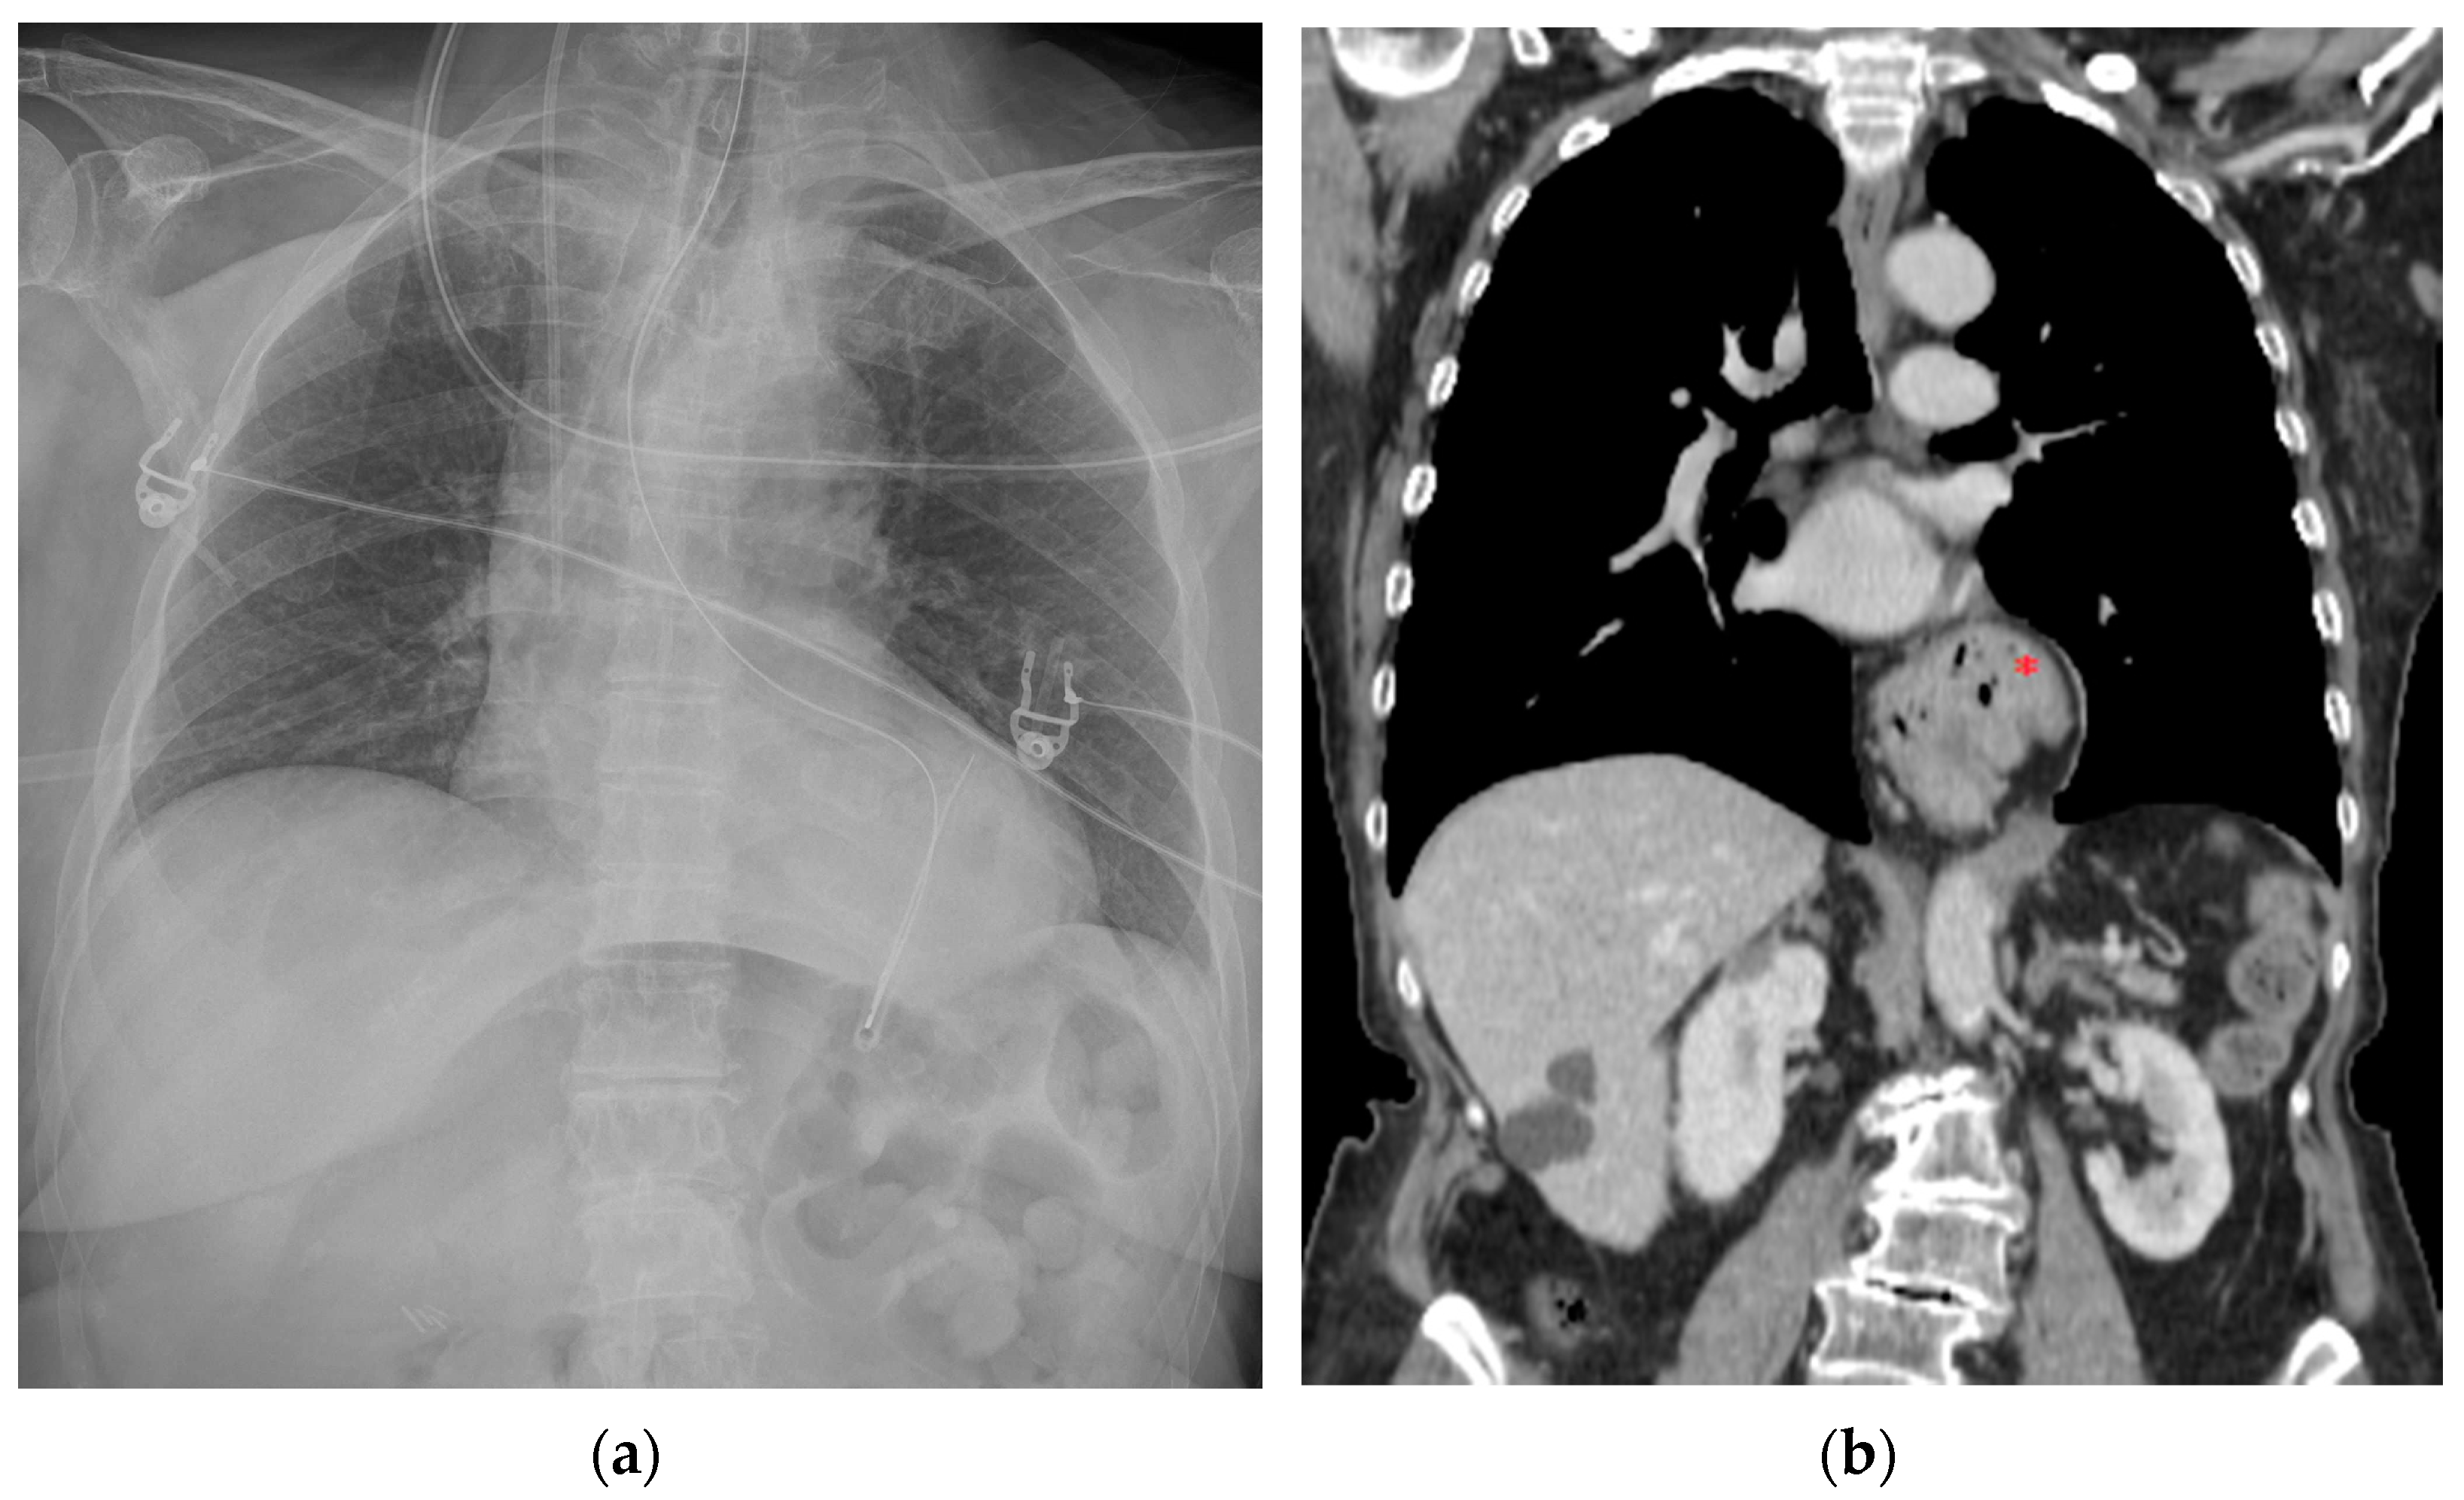

The following section discusses a series of CXRs depicting other cardiac devices that are not included in the previously mentioned ones (Figure 18, Figure 19 and Figure 20).

Figure 18.

This CXR shows the result of a transcatheter aortic valve implantation (TAVI) (green arrow). The radiogram also includes a PM, a tracheostomy tube and a right jugular CVC.

Figure 20.

Left atrial appendage closure device (red asterisk). Prosthetic biological mitral valve (green asterisk). the image also shows right jugular CVC, ETT, NG-tube, chest tubes and sternal wires.